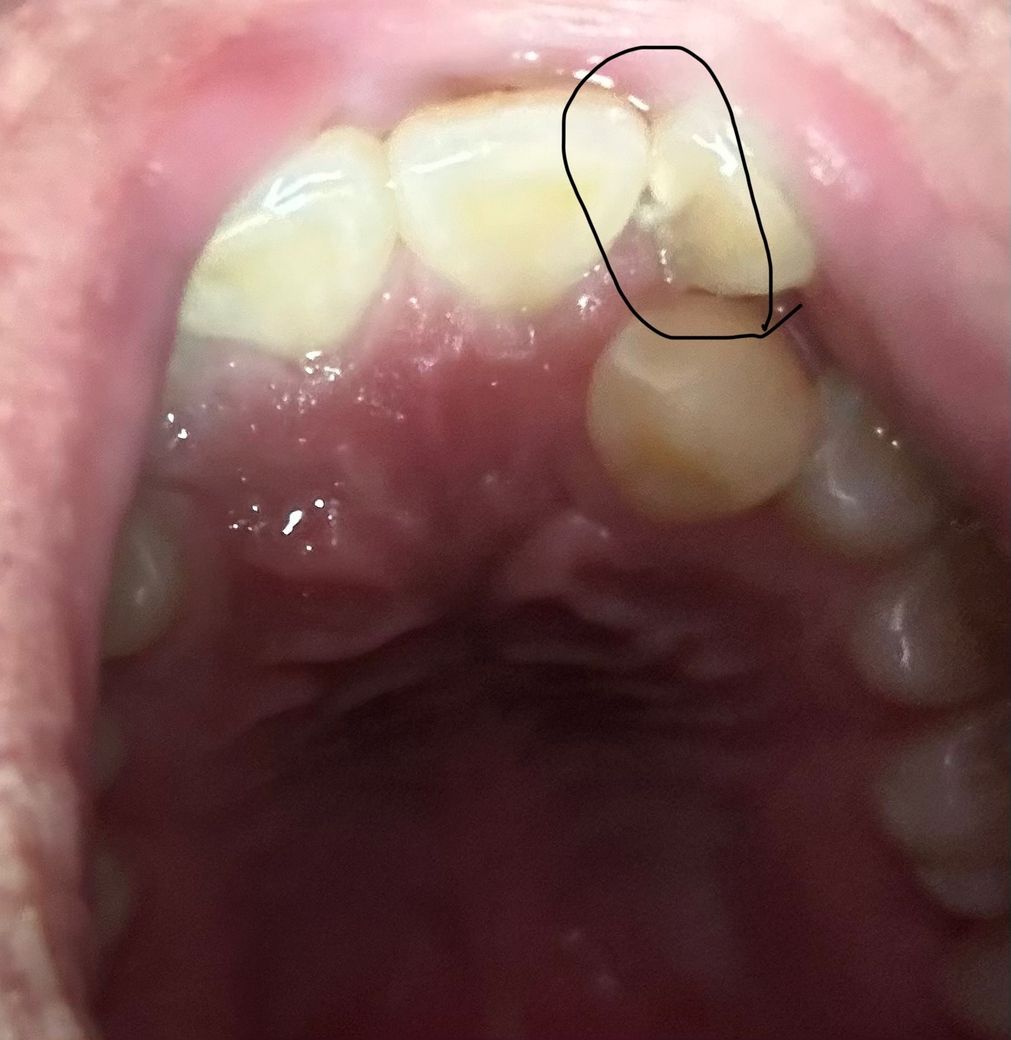

오늘 점심먹고 혀로 갖다대봤는데 뭔가 걸리는게 있어서

사진 찍어봤는데 이렇게 되어있네요 깨진건지 벌어진건지..

충치 맞습니다 그쪽 치열이 고르지 않아 음식물이 잘 껴 충치가 잘 생길수밖에 없는 조건이긴하네요

네 충치가 맞고, 사이즈도 꽤 커보입니다. 저 부분은 치아배열이 들쑥날쑥해서 양치질을 깨끗이 하기 어려워 충치가 생기기 쉬웠을 것입니다. 빠른 시일내에 치료 받으시고 , 저 부분은 칫솔방향을 이리저리 돌려가면서 작은앞니 뒷면도 확실히 닦을 수 있도록 해주셔야겠습니다. 그게 어려우시다면 첨단칫솔을 사용해서 닦아주시면 좀 편하실 것입니다. 그리고 치실사용 꼭 해주셔야합니다.

충치같아요~ 치과치료는 미룰수록 범위가 더 커지니 미루시지 마시고 치과 가셔서 검진받아보세요!

충치로 인해 치아가 부식되어 깨진것으로 보여집니다. 치과에 내원하여 확인하면 좋을것같습니다. 건강하세요.